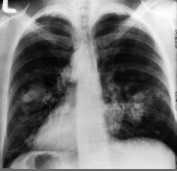

Un dépistage plus systématique du cancer du poumon à l'aide d'un scanner à faibles radiations pourrait détecter des dizaines de milliers de cancers du poumon supplémentaires dans les cinq prochaines années aux Etats-Unis, mais à un coût élevé, selon des chercheurs.

Ils préconisent un scanner annuel, au lieu d'une radiographie pulmonaire, pour les personnes de 55 à 80 ans ayant fumé au moins 15 paquets de cigarettes par an durant leur vie, fument encore ou se sont arrêtées dans les 15 dernières années.

Une application progressive de ces recommandations permettrait de détecter près de 55.000 cancers du poumon supplémentaires, dont la plupart à un stade précoce donc plus traitables, avec une plus grande chance de survie.

Selon l'USPSTF, il est possible de faire reculer la mortalité de 20% chez les patients à hauts risques grâce à un tel dépistage.